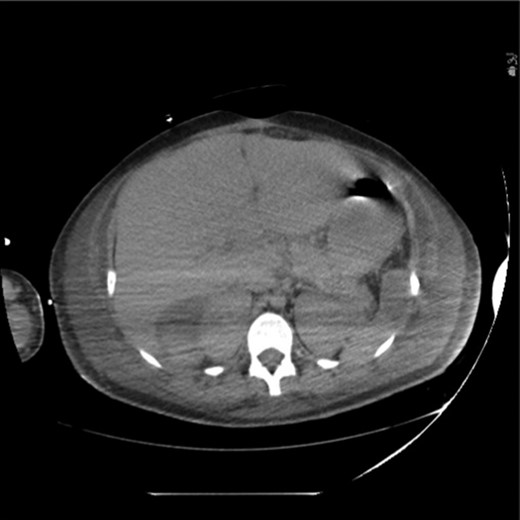

On the evening of post-burn day (PBD) 2, the patient developed a distended abdomen and became oliguric, unresponsive to volume challenge. A portable abdominal x-ray was concerning for pneumatosis of the stomach, small bowel and colon (Fig. 2). Computed tomography (CT) confirmed pneumatosis of the esophagus, stomach, small bowel and much of the colon, and hepatic portal venous gas (HPVG)—concerning for ischemic bowel (Fig. 3A–C) and prompting operative intervention. Of note, all vessels were patent. In the operating room (OR), the GI tract was distended with pneumatosis but without signs of ischemia except for a segment of mid-jejunum which was resected. She became hemodynamically unstable and thus left in discontinuity and an open abdomen.

CT showing extensive pneumatosis involving the esophagus (A), the stomach (B) and the small bowel and colon (C). Hepatic portal venous gas is notable in (B).